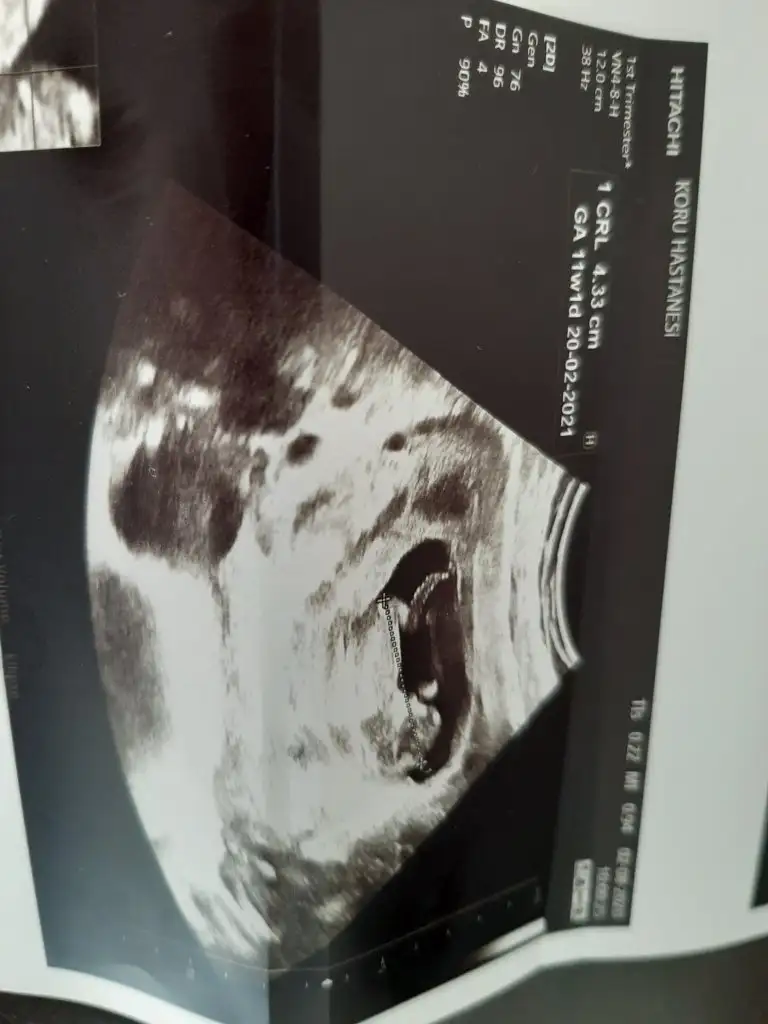

Nub teorisi

Merhaba ikili test görüntüsü varsa daha iyi olur burdan anlaşılmıyor. Tam nuba bakılacak yere doktor işaret koymuş boy ölçmek için. Ya da ben göremiyorum :)